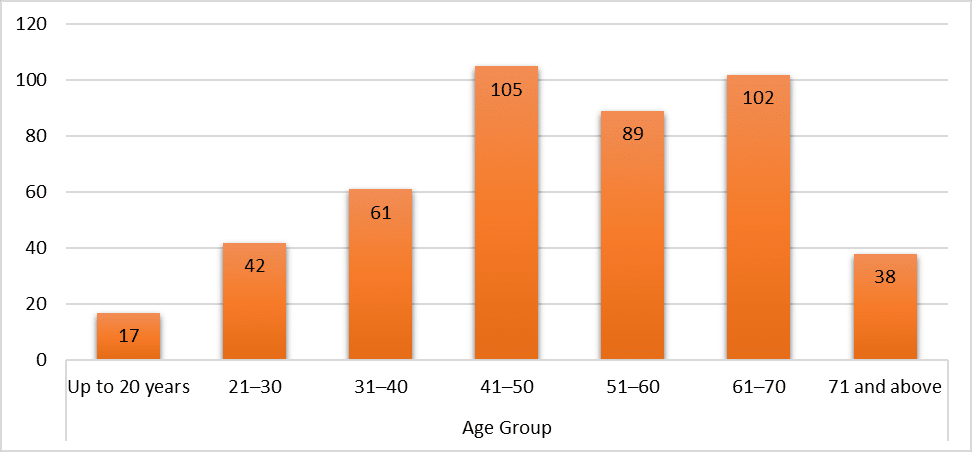

Dermatology | May 20, 2025

Identification of Risk and Associated Factors of Pressure Ulcer among Hospitalized Patients in Karachi

Background: Pressure ulcers are a common health problem and are considered a burden on the health care system. They manifest...Read More